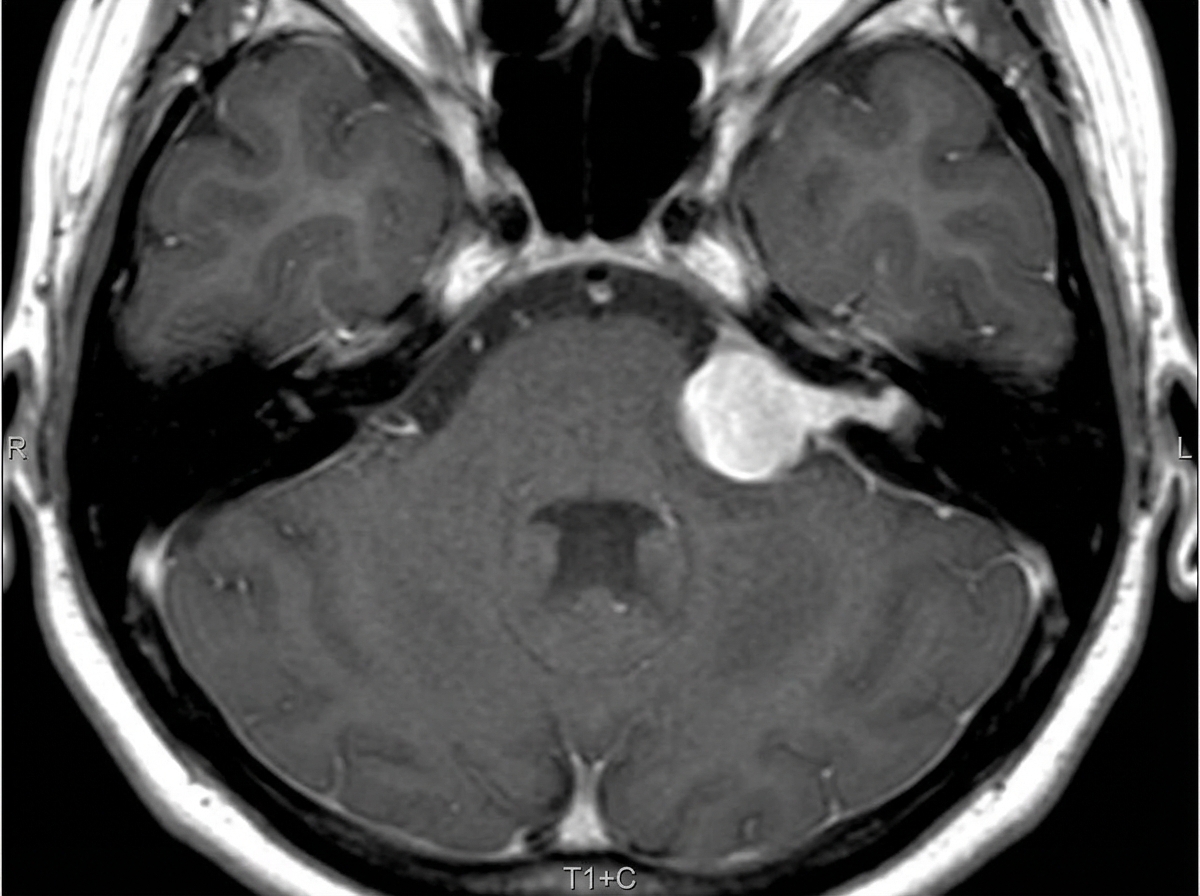

This classical "Ice-cream cone" appearance of an intensely enhancing lesion at the right CP angle recess suggests:

Explanation: ***Acoustic schwannoma*** - The classical **"ice-cream cone"** appearance consists of intense enhancement with the **cone portion extending into the internal auditory canal (IAC)** and the **ball portion in the CP angle cistern**. - **Acoustic schwannomas** characteristically show **homogeneous intense enhancement** and have a predilection for the **cerebellopontine angle** with IAC extension. *Epidermoid cyst* - Epidermoid cysts typically show **no enhancement** or minimal rim enhancement, unlike the intense enhancement described. - They appear **hyperintense on DWI** and follow **CSF signal** on T1 and T2, not showing the solid enhancing pattern. *Arachnoid cyst* - Arachnoid cysts show **no enhancement** and perfectly follow **CSF signal intensity** on all sequences. - They appear as **simple fluid collections** without the solid enhancing mass characteristic of the ice-cream cone sign. *High grade glioma* - High grade gliomas rarely occur at the **CP angle** and typically show **heterogeneous enhancement** with necrosis and surrounding edema. - They demonstrate **ring enhancement** or irregular enhancement patterns, not the homogeneous intense enhancement of acoustic schwannomas.